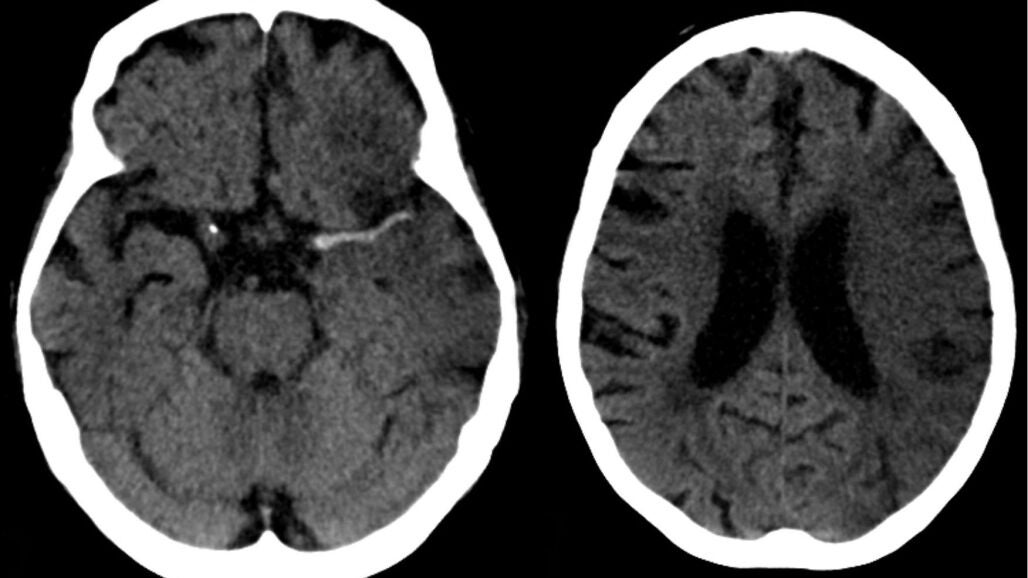

"Cualquier enfermedad que tenga un impacto sobre las arterias -incide Castro- tiene un efecto más rotundo en las arterias de las mujeres", y sus consecuencias varían dependiendo de la zona que ha afectado al vaso infartado, del tiempo que ha estado el cerebro sin recibir sangre y del daño que ha producido.